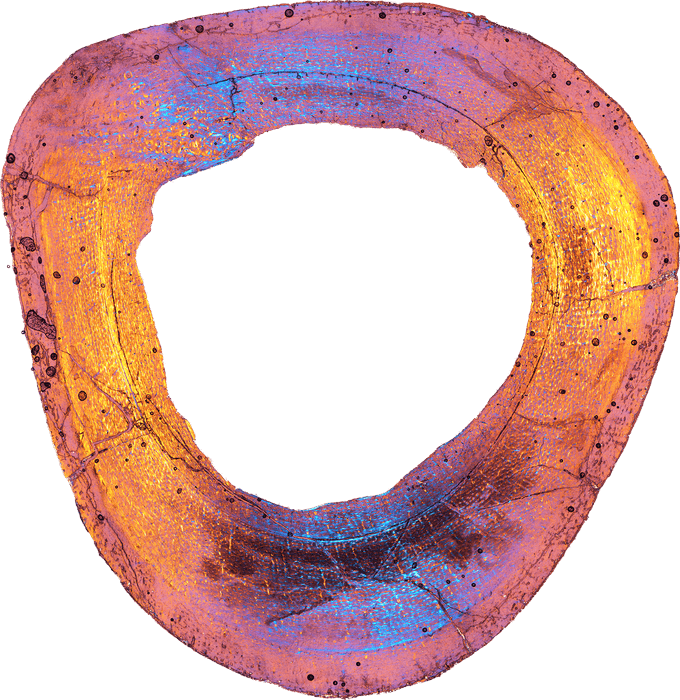

研究グループが脚の骨を薄く切り出して、木の年輪のような成長線を調べたところ、2歳以上の若い個体だったことが判明。体重は約6㌔、体長は1㍍と推定しています。